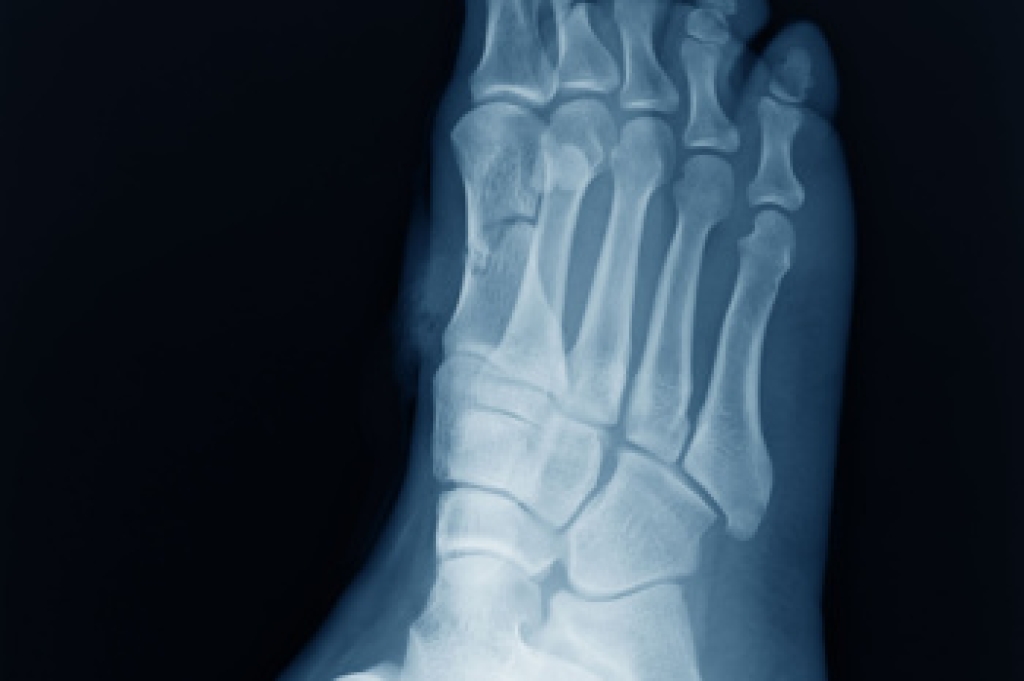

Diagnosis

Diagnosis of cuboid syndrome is often difficult, and it is often misdiagnosed. X-rays, MRIs and CT scans often fail to properly show the cuboid subluxation. Although there isn’t a specific test used to diagnose cuboid syndrome, your podiatrist will usually check if pain is felt while pressing firmly on the cuboid bone of your foot.